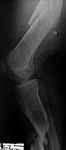

Here is a close up of the regenerate under hot light. There is a small amount of wispy regenerate. Would you continue advancing? Ive placed a bone stim over the regen site. Most likey will convert to nail.

JN> Here is a close up of the regenerate under hot light. There is a small amount of wispy regenerate. Would you continue advancing?

Expected time of maturation looks too long so in case of ex-fix as definitive stabilization i would prefer to drop distraction back and re-do corticotomy higher, at the middle of the segmental fragment.